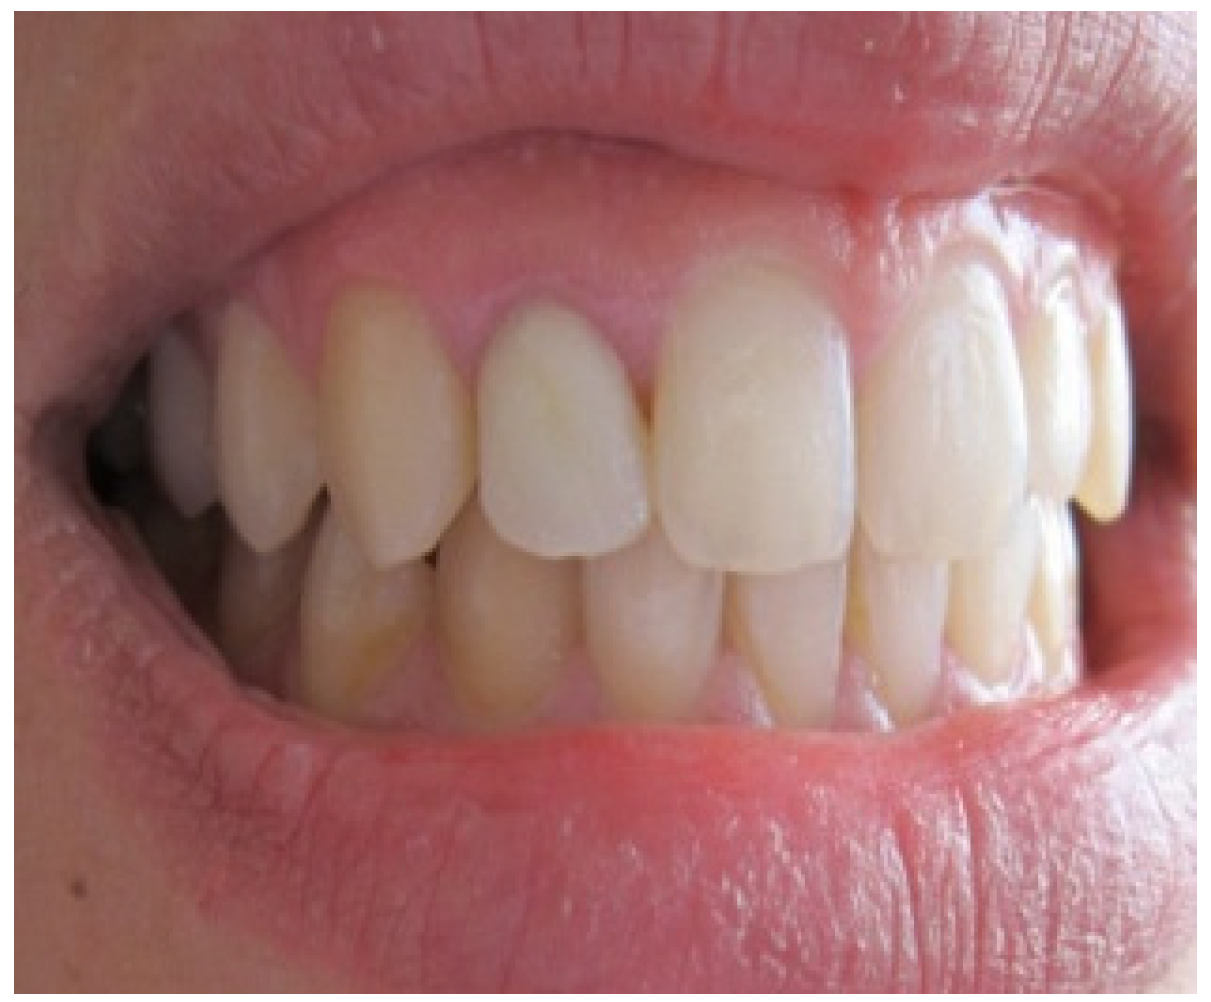

A 25-year-old dental student presented to the department of prosthetic dentistry with a chief complaint of poor aesthetics due to her imperfect metal ceramic single crown in the lateral incisor. She was bothered about the visible dark areas under the crown margins and requested an aesthetic rehabilitation. She also expressed her dissatisfaction with its color and shape. Intra oral examination showed dark gingival margins in the lateral incisor caused by metal frame (Figure 1). Soft tissues were evaluated as healthy with a wide band of attached gingiva in the maxillary region and a good oral hygiene.Visual assessment and Periodontal probing revealed a thick healthy gingival biotype with gingival thickness of 2 mm. and a sulcus depth of 2 mm. Bone sounding revealed a crest position in close relationship relative to anticipated post-surgical gingival margin level (2.5 mm). As the patient presents a thick periodontal biotype, this would significantly influence the post-operative procedure in favor of the esthetically desired outcome as this type is less prone to post-surgical recession.

Aesthetic assessment showed a squared teeth form, a size discrepancy and a non-symmetrical gingival architecture between the left and right lateral incisors (Figure 2). A slight asymmetry between the gingival margins of the right and left central incisors was noticeable. However, the patient did not express her dissatisfaction about it and refused any surgery on her sound teeth.

Figure 1. Intra oral view showing the grayish shadow caused by the metal based crown.

Figure 2. Gingival display due to the asymmetrical ZENITH.